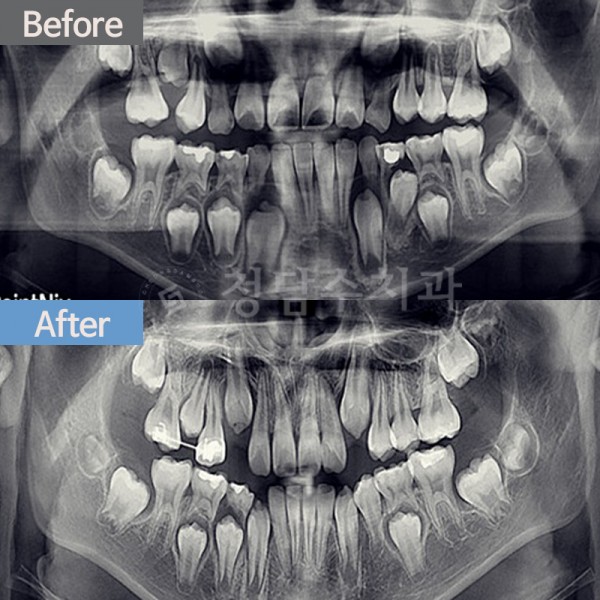

치아교정 어린이 교정

어린이 교정